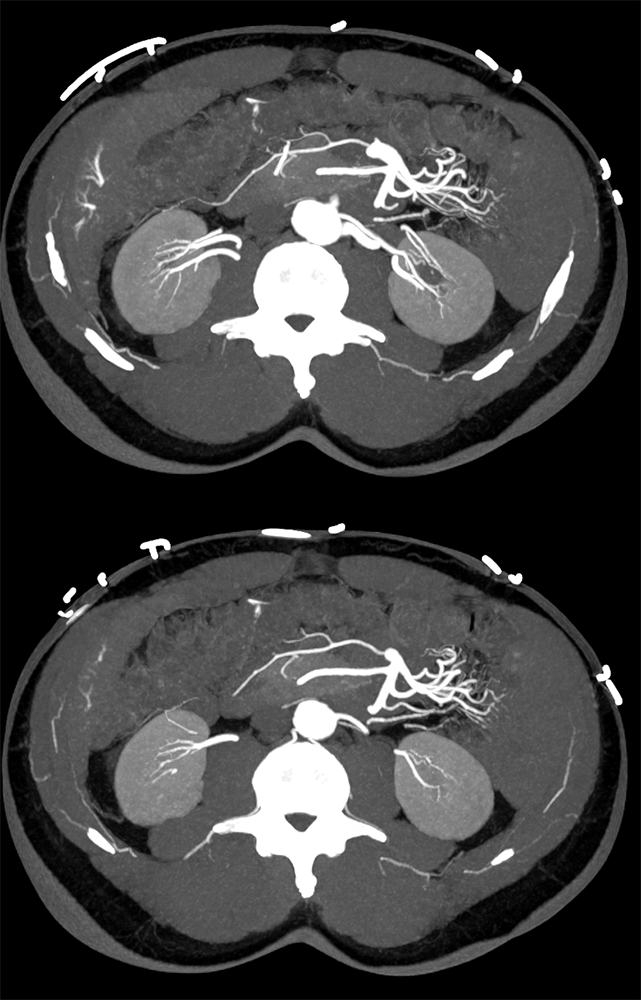

Vascular Foci in Duodenum: Angiodysplasia ![]() |

![]() |